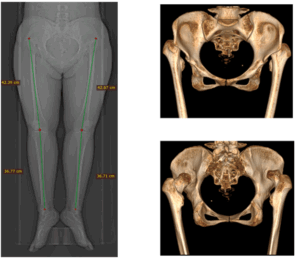

Разработана анатомическая пластина для надлодыжечной остеотомии большеберцовой кости, учитывающая особенности дистального отдела и позволяющая минимизировать травматичность доступа. Механические испытания подтвердили устойчивость конструкции, а первые клинические наблюдения выявили улучшение функциональных показателей и коррекцию оси конечности. Клинический этап продолжается.

- Тажин К. Б., Нурахметов А. А. Асқаров Н. Л., Косубаев А. Л. Надлодыжечная остеотомия большеберцовой кости для профилактики ассиметричного крузартроза // Traumatology and Orthopаedics of Kazakhstan. – Астана. – 2024. – Volume 75. — N 4. – С. 19-25.